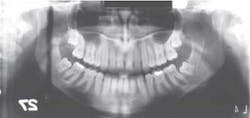

Last month we asked you to Diagnose the X-ray below and send in your answers on what you think the operator may have done wrong. Today we provide you with the image's diagnosis!We would like to congratulate Chris Beadle for correctly diagnosing the below image and winning a $25 gift card. Chris is a territory rep in the Nashville, Tenn., area for Patterson Dental Supply. Be sure to send in your diagnosis for this month’s Diagnose the X-ray for a chance to win!Let me explain how the problem can occur, and how you can correct it.

X-ray answer ...The dark vertical line extending from the top to the bottom of the film was caused when the cassette was rotating around the patient during exposure and temporarily stopped when the cassette hit the patient's shoulder. When the cassette stopped, the film received additional exposure, thus creating the dark vertical line. Film exposing and handling tips:

- Would be considered a patient slumping error

- Have patient stand up straight and straighten neck

- Have patient keep elbows tucked in to reduce shoulder height

- Check lead apron for interference